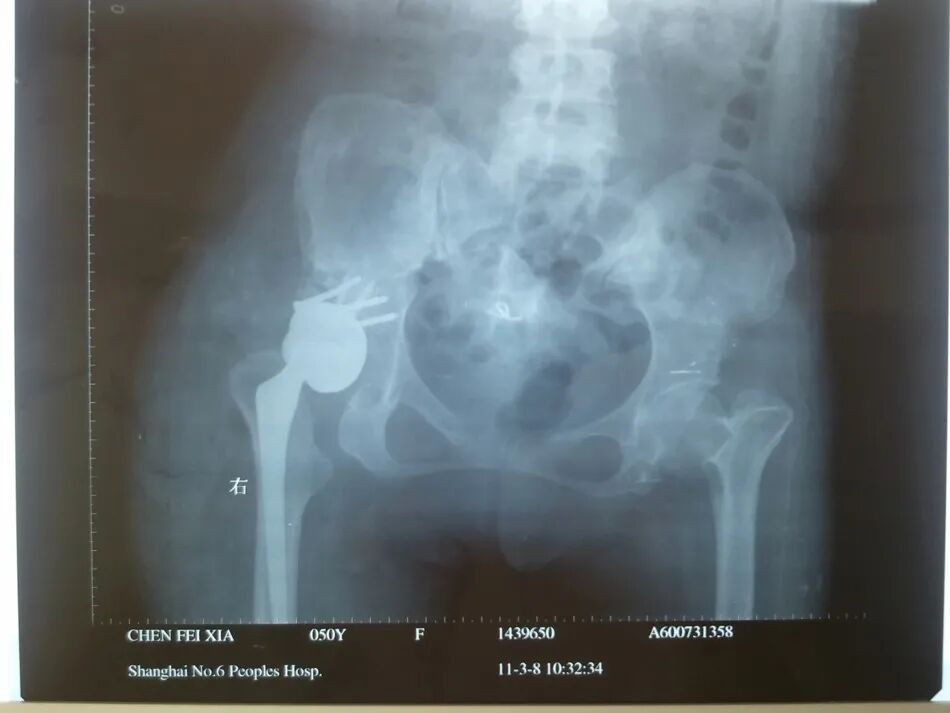

女性患者,48岁,右髋疼痛25年,加重1年

术后5天,脱位